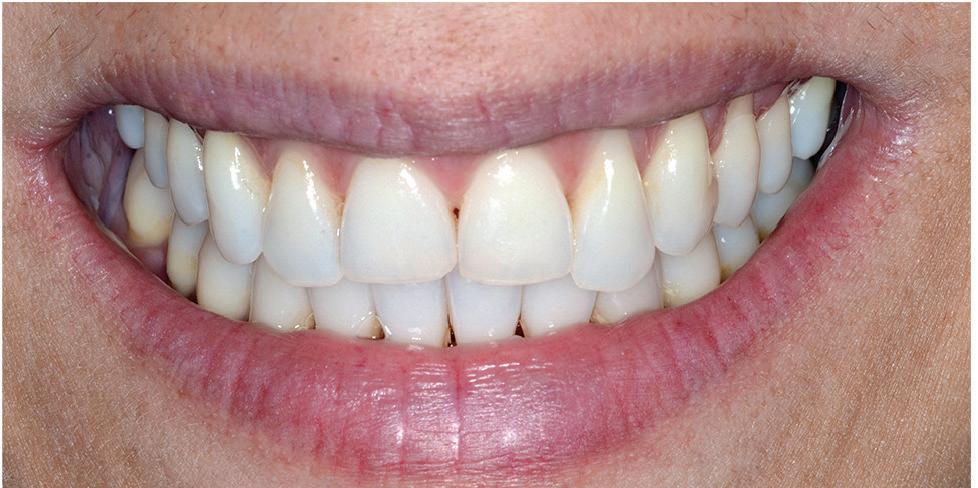

VITA In-Ceram® (VITA Zahnfabriek, Germany) all-porcelain crowns were placed after a further 4 months of healing and tissue maturation, with a good aesthetic outcome (Figure 16).

The patient was followed up at regular intervals and after 15 years the anterior 6 crowns (13-23) were replaced due to marginal fractures of the In-Ceram® crowns on the palatal aspects.

The periodontal tissues are stable at 25 years (Figure 17). This case demonstrates a stable long-term result of performing extensive aesthetic crown lengthening utilizing a two-stage surgical protocol with a predictable step-by-step treatment. This allowed full control and minimal loss of attached gingiva, due to at least 2-3 mm of lengthening obtained from the process of recession.

Figure 16: Six months after placing final crowns. Figure 17: 25 Years after surgery, showing stable gingival margins.